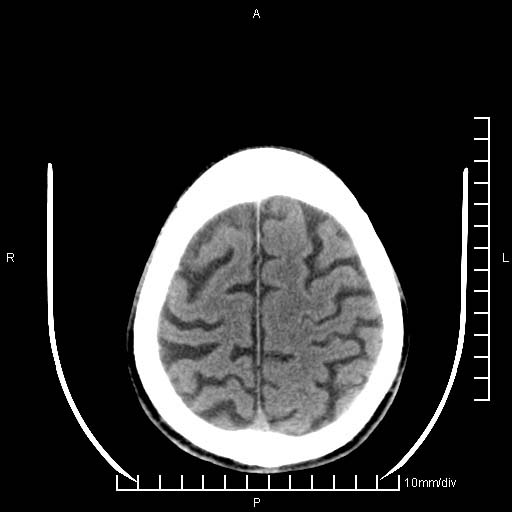

临床以双下肢浮肿,疼痛收治,无明显神经系统症状,既往无梗塞,出血病史。左颞叶见低密度灶,考虑什么?

考虑左侧颞叶脑软化灶。

无强化 无占位 软化灶吧

无强化、 无占位、局部脑沟增宽, 软化灶吧。